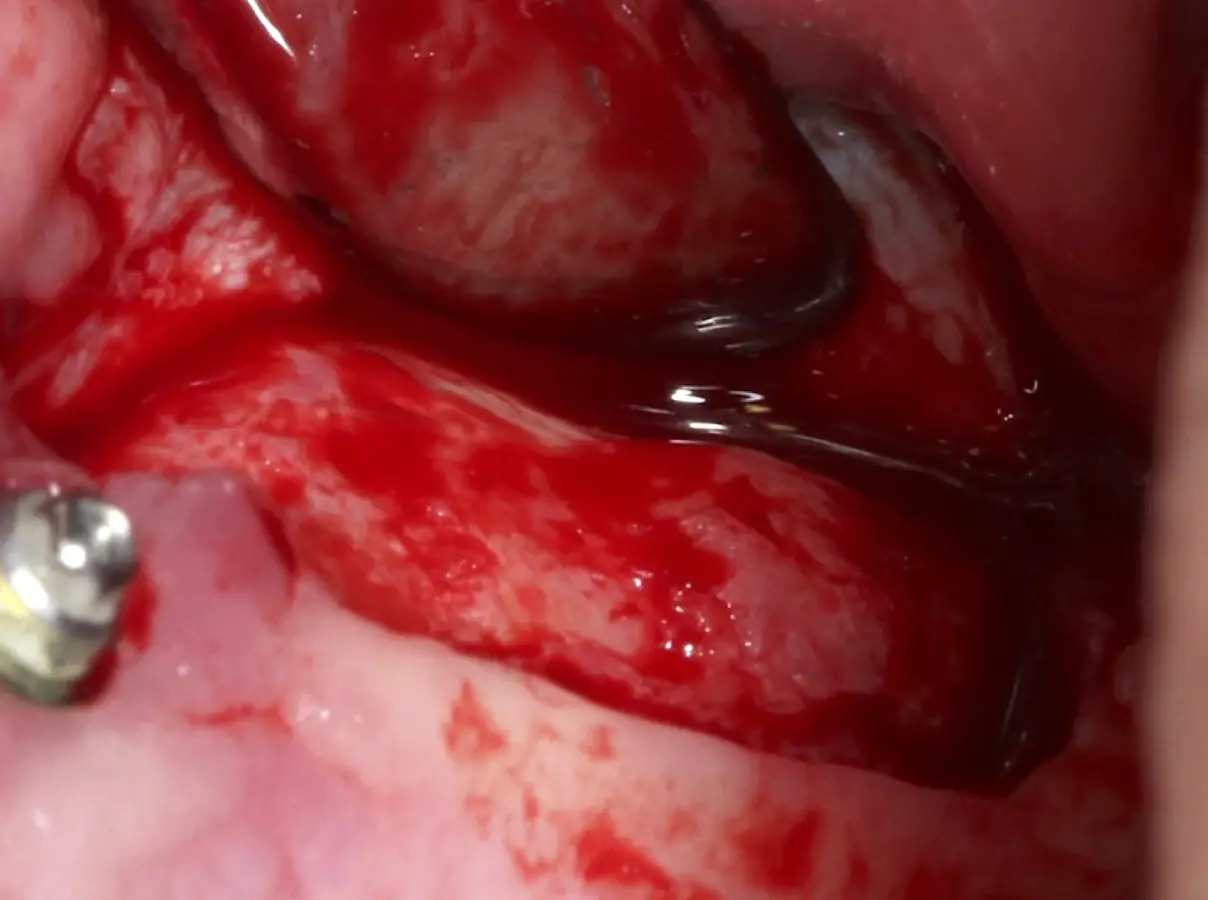

Figura 26. Decolado de la membrana de Schneider hasta la pared medial del seno maxilar (a). Desplazamiento de la pared ósea lateral al interior del seno maxilar transformándose en parte del techo de la ventana o nuevo piso del seno (b).